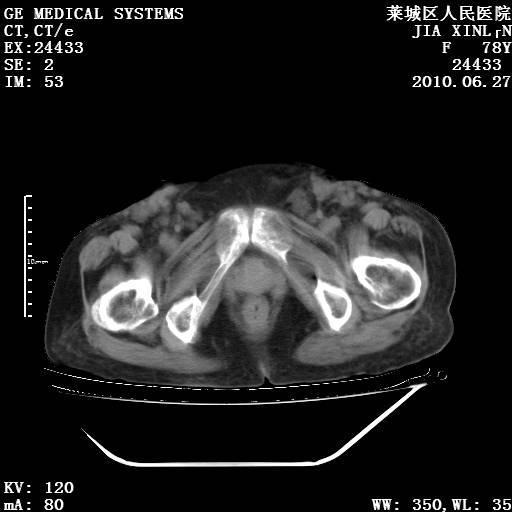

以下是引用胡宇在2010-7-2 19:11:00的发言:[br]神经纤维瘤的特点为:肿块呈多发性、数目不定,少的几个,多的可成百上千难以计数。小的如米粒,大的似拳头,甚至可达十数公斤以上。可松弛地悬挂于皮表,皱褶及松弛可致畸形明显。神经纤维瘤沿神经干的走向生长时呈念珠状,或蚯蚓块状形结节。此外神经纤维瘤皮肤可出现咖啡斑,大小不一,形如雀斑小点状,或大片状,分布与神经纤维瘤肿块的分布无关。肿瘤数目不多的患者,皮肤色素咖啡斑状沉着是纤维神经瘤的重要诊断之一。 本病多发于躯干,有时出现于四肢及面部,患者常合并许多疾病应予重视加以区别。 [br] [br] [br] [br]lyb999说 [br]